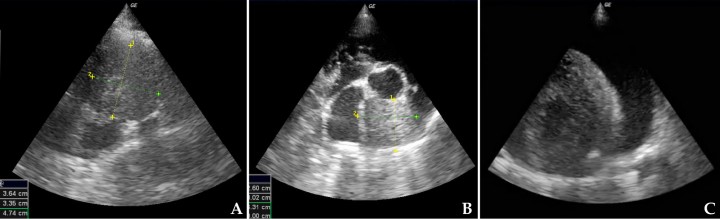

Ecocardiografía

La ecocardiografía tiene una alta especificidad (100 %) y sensibilidad (82 %) para el diagnóstico de masas cardiacas y derrames pericárdicos.[ MacDonald KA, Cagney O, Magne ML: Echocardiographic and clinicopathologic characterization of pericardial effusion in dogs: 107 cases (1985-2006). J Am Vet Med Assoc 2009; 235:1456-1461. [PubMed] ]

Tanto el tamaño como la localización puede ayudar al diagnóstico, siendo siempre necesario la citología o la toma de biopsias para la confirmación del diagnóstico.[ Rajagopalan V, Jesty SA, Craig LE, Gompf R: Comparison of presuntive echocardiografic and definitive diagnosis of cardiac tumours in dogs. J Vet Intern Med 2013;27(5):1092-6. [PubMed] ] Las masas cardiacas pueden tener cualquier localización cardiaca (Fig. 7).

Los hallazgos más comunes son:

1. Masas heterogéneas redondeadas en aurícula derecha (p. ej., hemangiosarcoma) (Fig. 8A).

2. Tumores de base cardiaca (p. ej., quemodectoma), que son de aspecto más homogéneo y se suelen encontrar en el cayado de la aorta o localizados entre el tronco pulmonar y la aorta, observándose sobrecarga de volumen ventricular derecha por colapso de las venas pulmonares (Fig. 8B).

3. Derrame pericárdico con/sin signos de taponamiento cardiaco. En el taponamiento cardiaco observamos colapso de la pared libre del atrio y/o del ventrículo derecho. Un taponamiento grave puede producir una reducción del volumen del ventrículo izquierdo apreciándose una pseudohipertrofia de ventrículo izquierdo (Fig. 8C).

4. Los mesoteliomas o tumores de pequeño tamaño pueden ser más difíciles de visualizar. Sin embargo, ocasionalmente se puede observar, además de derrame pericárdico, pequeños filamentos que surgen del ventrículo izquierdo (Fig. 9).

<p>(<strong>A</strong>) Ecocardiografía en corte paraesternal derecho eje corto, base cardiaca-aorta compatible con masa en atrio derecho. (<strong>B</strong>) Ecocardiografía en corte paraesternal derecho eje corto, base cardiaca-aorta compatible con tumor de base cardiaca. (<strong>C</strong>) Ecocardiografía en corte paraesternal derecho eje corto, ventrículo izquierdo compatible con derrame pericárdico.</p>

(A) Ecocardiografía en corte paraesternal derecho eje corto, base cardiaca-aorta compatible con masa en atrio derecho. (B) Ecocardiografía en corte paraesternal derecho eje corto, base cardiaca-aorta compatible con tumor de base cardiaca. (C) Ecocardiografía en corte paraesternal derecho eje corto, ventrículo izquierdo compatible con derrame pericárdico.

<p>(<strong>A</strong>) Ecocardiografía en eje paraesternal derecho, eje corto, ventrículo izquierdo, compatible con derrame pericárdico y mesotelioma. (<strong>B</strong>) Detalle <em>post mortem</em> de mesotelioma.</p>

(A) Ecocardiografía en eje paraesternal derecho, eje corto, ventrículo izquierdo, compatible con derrame pericárdico y mesotelioma. (B) Detalle post mortem de mesotelioma.